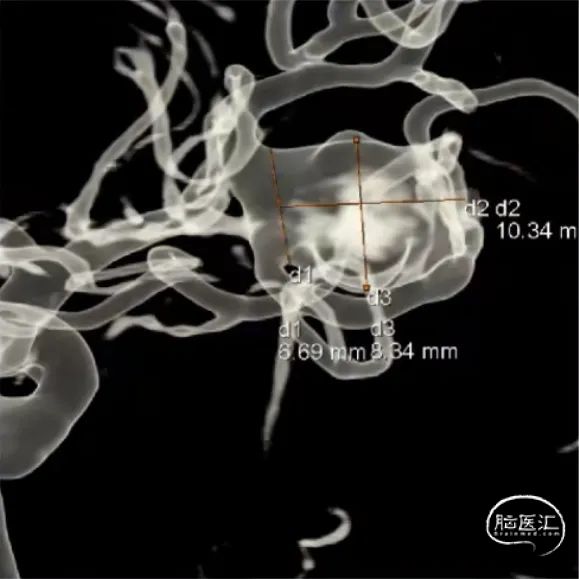

经测量可得动脉瘤宽度平均值为8.88mm,动脉瘤最小高度为7.71mm,瘤颈约为4.03mm。参考尺寸选择表,选择WEB™ SL 10*5,VIA™ 33微导管。

经测量可得动脉瘤宽度平均值为7.0mm,动脉瘤高度为7.4mm,最终选择WEB™ SL 9*6。

经测量可得动脉瘤宽度平均值为9.1mm,动脉瘤最小高度为8.9mm,最终选择WEB™ SL 11*6。